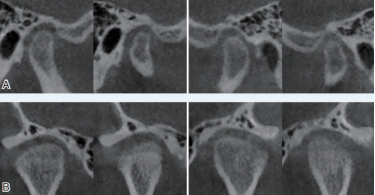

(口腔颌面外科医生可以通过CBCT观察患者两侧颞下颌关节的情况)